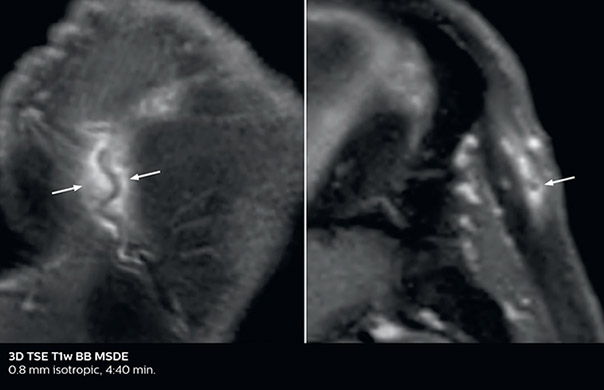

So, what is the actual impact of having more information and more diagnostic confidence? According to Dr. Savatovsky, “One of the indications I’ve seen where using Elition is most impactful is in patients with suspected giant cell arteritis. As an ophthalmologic hospital, we see many patients with suspected giant cell arteritis. Usually we were performing MRI to help us rule out an ischemic stroke, and to verify that the supra aortic vessels are undamaged. With Elition, we still do this, but now we can add on more detailed high-resolution black-blood sequences on superficial arteries. This provides us with high confidence levels for diagnosis of giant cell arteritis (GCA) and as a result, some patients are not sent for a biopsy anymore. A patient who has a normal MRI will not require a biopsy and can be discharged from the hospital in the same day. Before, such a patient would have to stay for about a week, just to find that their biopsy results were negative. We have at least three or four patients a week with suspected giant cell arteritis. For a great deal of these patients we can have a direct impact on their hospital stay.”

Giant cell arteritis

The 3D TSE T1w black blood MSDE sequence with fat suppression has an isotropic 0.8 mm voxel size and sagittal oblique and axial reformats are made. The images show superficial temporal artery thickening and peri-arterial fat infiltration. The 3D TSE PDw black blood MSDE with fat suppression has 0.55 mm isotropic voxels. The images shows focal involvement of the frontal branch of the superficial temporal artery.

3D TSE T1w BB MSDE

3D TSE PDw BB MSDE